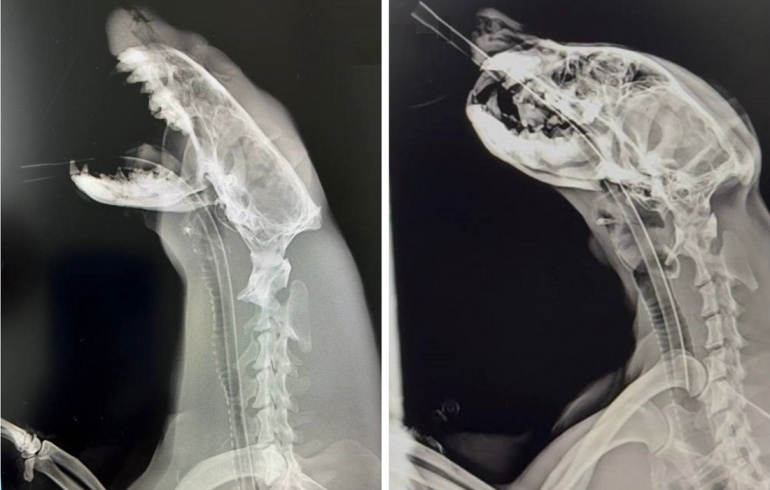

— На этом все, собственно, хотели выдохнуть, но не особо получилось — через несколько дней у господина выдры (он же Ваня) прилично так раздуло щеку, — рассказали в зоопарке. — Вот прям так опухло, что глаз не открывался. Ветеринары предположили, что такую «красоту» мог дать зуб. Поэтому пришлось снова прибегнуть к пресловутому наркозу и обследовать парня вдоль и поперёк. Как итог — минус два зуба. Один просто дальний сбитый и плохой, а второй — воспалившийся клык, который и дал вот этот огромный отёк.

Для перестраховки клык отправили на гистологию, результат которой порадовал: просто сильное воспаление и прикорневая киста. Никакой злокачественности.